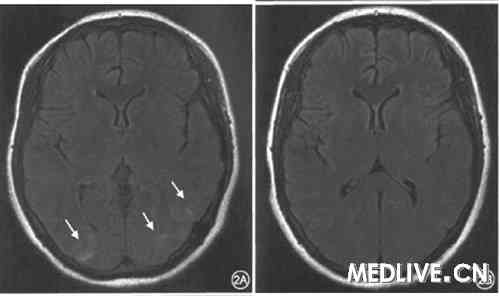

患者女,23岁,孕41周行剖宫产(孕1产1)娩出正常男婴。术后2 d出现双眼视力下降,伴轻度头痛,无惊厥发作,血压最高170/100 mmHg,于2008年4月9日前来就诊。既往孕36周产检发现血压高,150~160/90~100mmHg,未予特殊治疗。体格检查:血压150/90 mmHg。视力左眼0.1,右眼0.2;眼压:左眼19 mmHg,右眼21 mmHg;眼底视乳头边界清,视网膜无出血渗出,动静脉比例2:3,杯盘比0.3。双侧瞳孔等大等圆。直径约3 mm,直接、间接对光反射存在,眼球各方向活动正常,未发现神经系统局灶体征。头颅MRI检查,双侧枕、顶叶、右侧颢叶异常信号(图2A)。入院后给予解痉,降压,纠正低蛋白血症治疗。1d后视力恢复正常。3 d后复查头颅MRI,上述病灶消失(图2B)。出院诊断:可逆性后部白质脑病综合征(reversible posterior leukoencephalopathy syndrome,RPLS)。

图2皮质盲患者头颅MRI扫描轴位T2 Flair加权,2A示入院时检查。 可见双侧枕叶及左侧颞叶T2长信号(箭头);2B示经解痉、降压治疗3 d后复查,可见上述病变消失

可见双侧枕叶及左侧颞叶T2长信号(箭头);2B示经解痉、降压治疗3 d后复查,可见上述病变消失